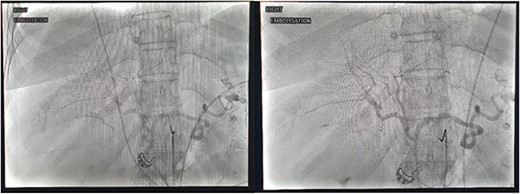

Right common femoral artery access was achieved, followed by Mickelson catheter access to celiac axis. Digital subtraction angiography (DSA) demonstrated active haemorrhage arising from the cystic artery (Fig. 2). A Renegade HiFlow microcatheter (Boston Scientific) was advanced into the cystic artery arising from the right hepatic artery. A repeat DSA in this position demonstrated multiple points of active haemorrhage around the gallbladder with two main branches arising from a central trunk. A single 3 × 3.3 mm Vortx coil (Boston Scientific) was deployed into the proximal cystic artery. A repeat DSA through the microcatheter in the right hepatic artery demonstrated the cessation of flow in the cystic artery and no further active haemorrhage (Fig. 2).

DSA images demonstrating active haemorrhage from the cystic artery and subsequent coil embolization with cessation haemorrhage.